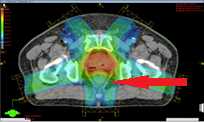

![]() |

|

| 通常照射(左)とIMRT(右) | 矢印の直腸の線量低減が見られる(IMRT) |